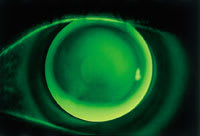

| Figure 1. Fluorescein pattern of the right eye | Figure 2. Fluorescein pattern of the left eye |

The RGP fitting was unremarkable (Figures 1 and 2); however, the patient complained of excessive lens awareness OU and an inability to maintain a consistent wearing schedule. In an attempt to enhance RGP adaptation, the patient was placed on a five-day course of Voltaren (diclofenac, Novartis).